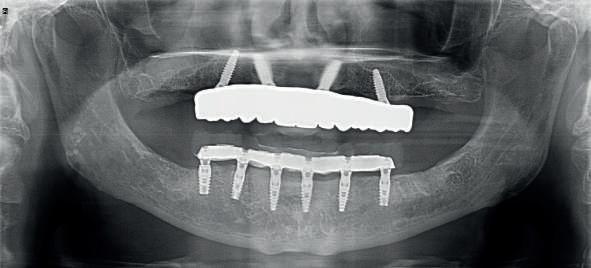

The immediate prostheses are milled in PMMA and fitted on their corresponding bases, adjusted and radiographically checked for proper seating.

After 6 months the patient returns and records are taken for the final prosthesis. In this case the lower prosthesis is made of a titanium bar and a PMMA superstructure and the upper part is made of a titanium substructure and a zirconia structure.